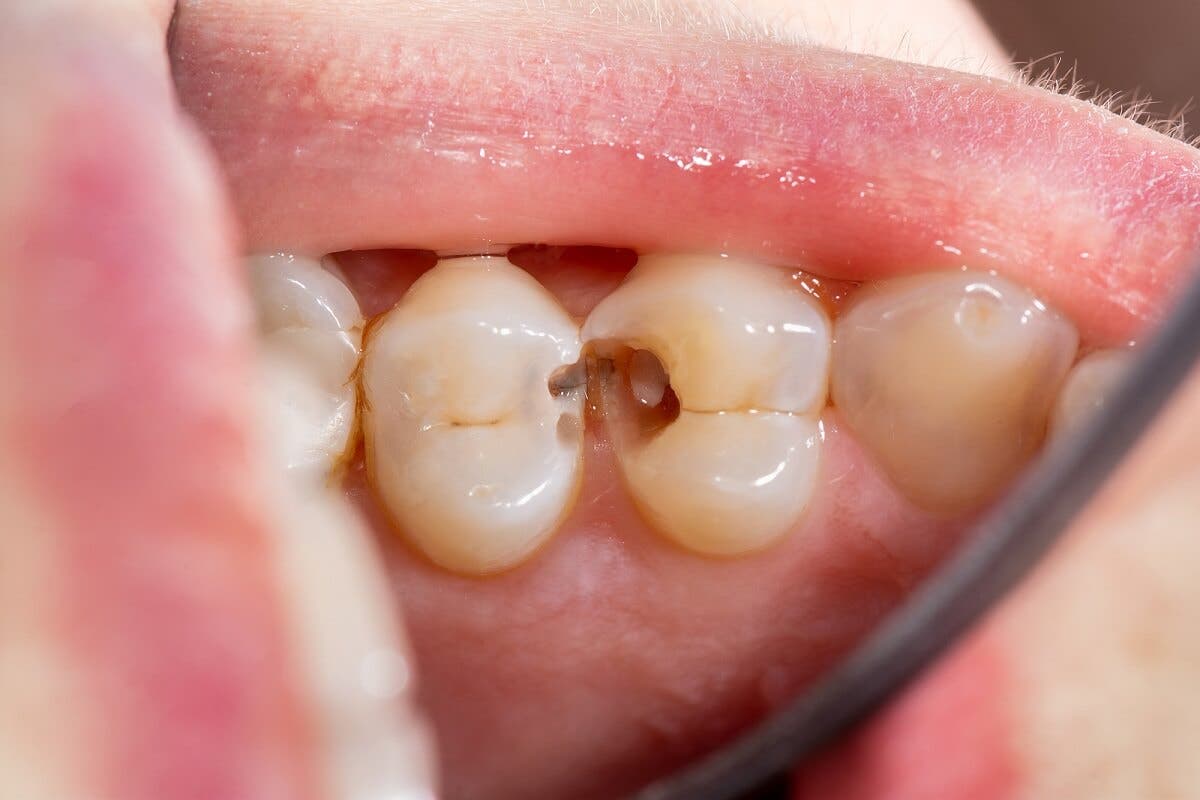

1. Tandbederf

Tandbederf is de meestvoorkomende mondziekte. Het treft mensen over de hele wereld, ongeacht geslacht en leeftijd.

Volgens de Global Burden of Disease Study 2019 is tandbederf in het blijvende gebit de meestvoorkomende mondaandoening. Ongeveer 2 miljard mensen lijden eraan en 520 miljoen kinderen lijden aan de ziekte in melktanden.

Tandbederf is de aantasting van de harde weefsels van de tanden. Ze verliezen hun mineralen door de werking van zuren die bacteriën in de mond produceren bij het metaboliseren van suikers in de voeding.

Slechte mondhygiëne en een dieet rijk aan eenvoudige koolhydraten zijn de belangrijkste factoren die in verband worden gebracht met het ontstaan van deze ziekte. Als er veel bacteriën in de mond zijn en ze genoeg suiker hebben om zich te vermenigvuldigen en steeds meer op te hopen, zal de zuurgraad in de mond de tanden beschadigen.

In het begin van de ziekte ziet tandbederf eruit als een droge witte vlek op het oppervlak van het tandglazuur. Naarmate het proces voortschrijdt, worden de vlekken donkerder, breekt het weefsel af, en ontstaan er gaten en holtes in de tanden.

Als holtes niet tijdig worden behandeld, kan de vernietiging de tandpulpa aantasten. Dit veroorzaakt pijn en infecties die de situatie verergeren en complexere behandelingen vereisen om ze op te lossen.

In een vroeg stadium kan tandbederf worden tegengegaan met fluoridetherapieën. Als er echter weefselverlies optreedt, zijn, afhankelijk van de omvang van het letsel en de ernst van het geval, vullingen, wortelkanalen of zelfs extractie van de tanden nodig.

Met gezonde gewoonten kan tandbederf worden voorkomen. Elke dag een goede mondhygiëne toepassen, fluoridetandpasta gebruiken, een suikerarm dieet eten en elke zes maanden de tandarts bezoeken zijn effectieve manieren om deze ziekte te voorkomen.